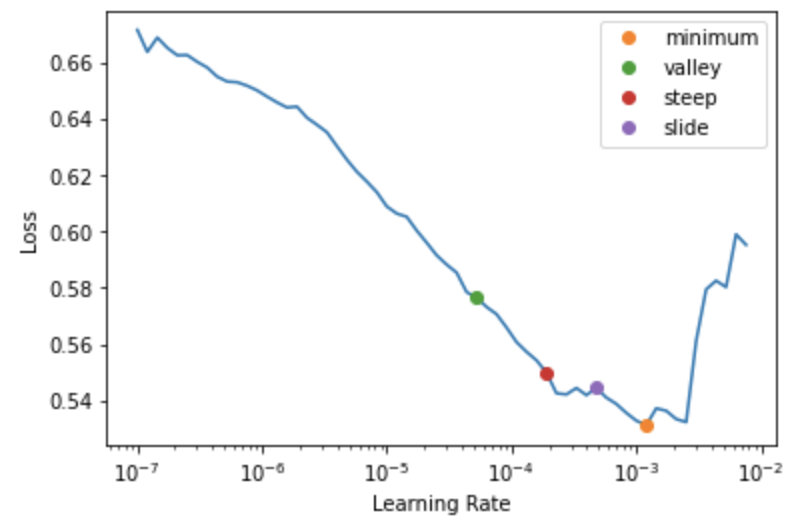

Learning rate